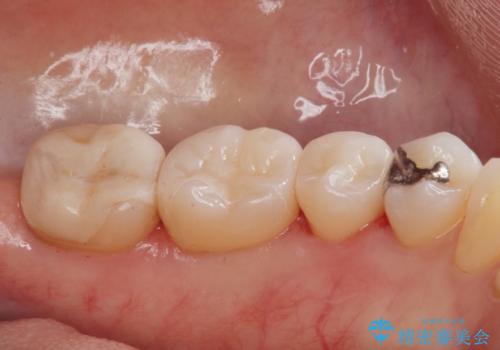

e-maxインレーは銀の詰め物に比べ歯との隙間ができにくく

虫歯の再発リスクが少ないです。

白い詰め物が入り満足して頂けました。